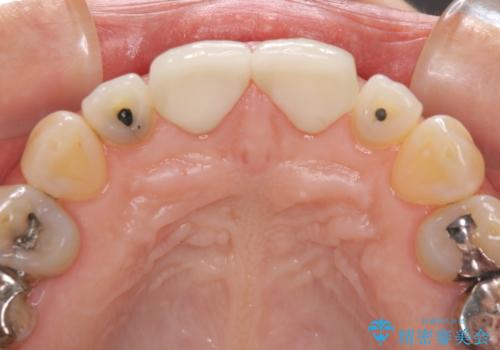

- 前歯のすきっぱを主訴にご来院された患者様です。他院でつめものやラミネートべニア(前歯の表面のみセラミックを貼り付ける)を行っていましたが、頻繁に外れることに悩まれており、クラウン(歯全体をセラミックがつつむ)をご希望されました。また、奥歯に大きな虫歯があり、歯が割れていたため、奥歯の治療も併せて行いました。

今回はまず欠けた場所を修復して見た目を回復させたのち、ラミネートべニアの仮歯をつくり、しばらく使用して考えて頂きました。メリットやデメリットを説明した結果、外れにくいセラミッククラウンをご選択頂きました。

咬み合わせや元のご自身の歯の色に特徴があったため、セラミッククラウンを修正したり、隣の歯を金属を外して白いつめものに変えたりして経過観察を長めに行いました。

右上の歯に関しても、大きな虫歯があったため、前歯の経過観察の間に治療を行いました。